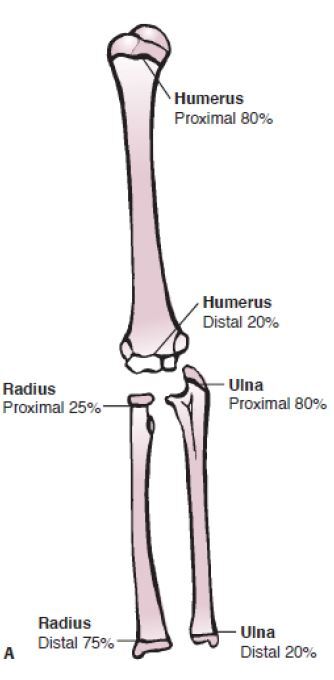

Percentual de crescimento dos MMSS?

A

How well did you know this?